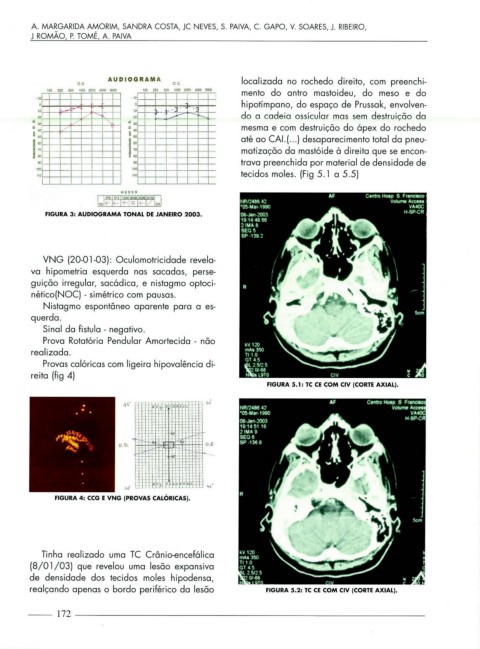

00 O. E. localizada no rochedo direito, com preenchi-

12S 250 125 150 500 1003 2000 ~ 80CO mento do antro mastoideu, do meso e do

o o • -3 ' - hipotímpano, do espaço de Prussak, envolven-

1-1-- - 1-- :>....-- ,...-- 1'--- do a cadeia ossícular mas sem destruição da

mesma e com destruição do ápex do rochedo

~r-- i-- - até ao CAl.( .. . ) desaparecimento total da pneu-

-- "i~ ~ matização da mastóide à direita que se encon-

--~ - trava preenchida por material de densidade de

o 11 o I I tecidos moles. (Fig 5.1 a 5 .5)

FIGURA S.l: TC CE COM CIV (CORTE AXIAL).

Tinha realizado uma TC Crâ nio-encefálico

(8/ 0 1 /03) que revelou uma lesão expansiva

de densidade dos tecidos moles hipodensa,

realça ndo apenas o bordo periférico da lesão FIGURA 5.2: TC CE COM CIV (CORTE AXIAL).